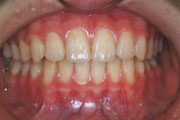

一般矯正の症例

症例2:乱杭歯(叢生)